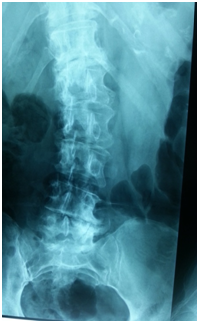

- Reduced normal dorsal kyphosis (Figure 1).

Figure 1 Compensation (Lumbar Kyphosis )à Decrease in S S ↑ Increase in PT, Hip Extension, Knee bend , Decrease in thoracic curve.